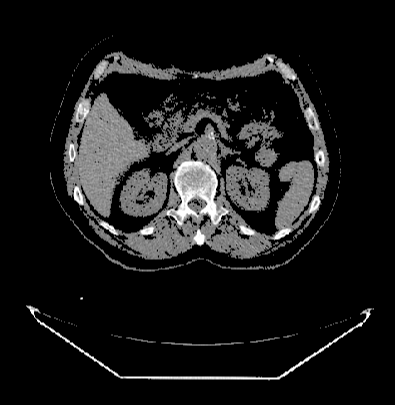

参考2(1)来设置对比度,在2(1)中讲到了DcmViewer医疗影像系统中的窗宽(window width)/ 窗位(window level、窗中心、窗口级别)的设置, 可以通过下拉框选取一个窗宽(window width)/ 窗位(window level、窗中心、窗口级别),通过调整窗宽(window width)/ 窗位(window level、窗中心、窗口级别)值,来增加VOl(Value Of Interest)区域的图像信息的对比度。

DcmViewer医疗影像系统可以设置整个视图的透明度, 设置区间为0-1, 这将设置整张图片的透明度。

默认值为1, 即整张图片不透明, 可以通过拖动滑块来设置这个透明度的值, 如设置为0.3的效果如下: